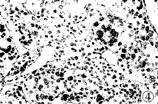

图3 同一病人术后标本作免疫组化微血管染色,发现癌边缘区有十分丰 富的微血管(×200)

图5 术后标本免疫组化微血管染色,显示癌边缘带微血管数目稀少(×100)